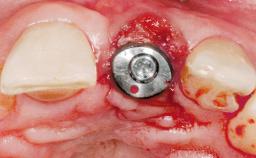

Late Placement of an Implant in a Maxillary Left Central Incisor Site

A 36-year-old female patient was referred for the replacement of the upper left central incisor (tooth 21), which had fractured. Although the tooth had been asymptomatic for many years, the crown began to loosen, at which time she presented to her dentist for an assessment. Teeth 21 and 22 had both been endodontically treated many years previously. She was a healthy individual and a non-smoker.

Bone Augmentation Horizontal|Staged

Bone Volume Deficient horizontally, requiring prior grafting